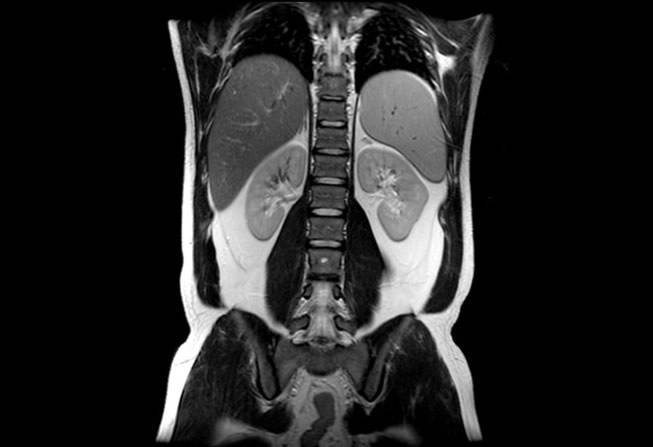

• Abdomen – Pelvis de Alta Resolución